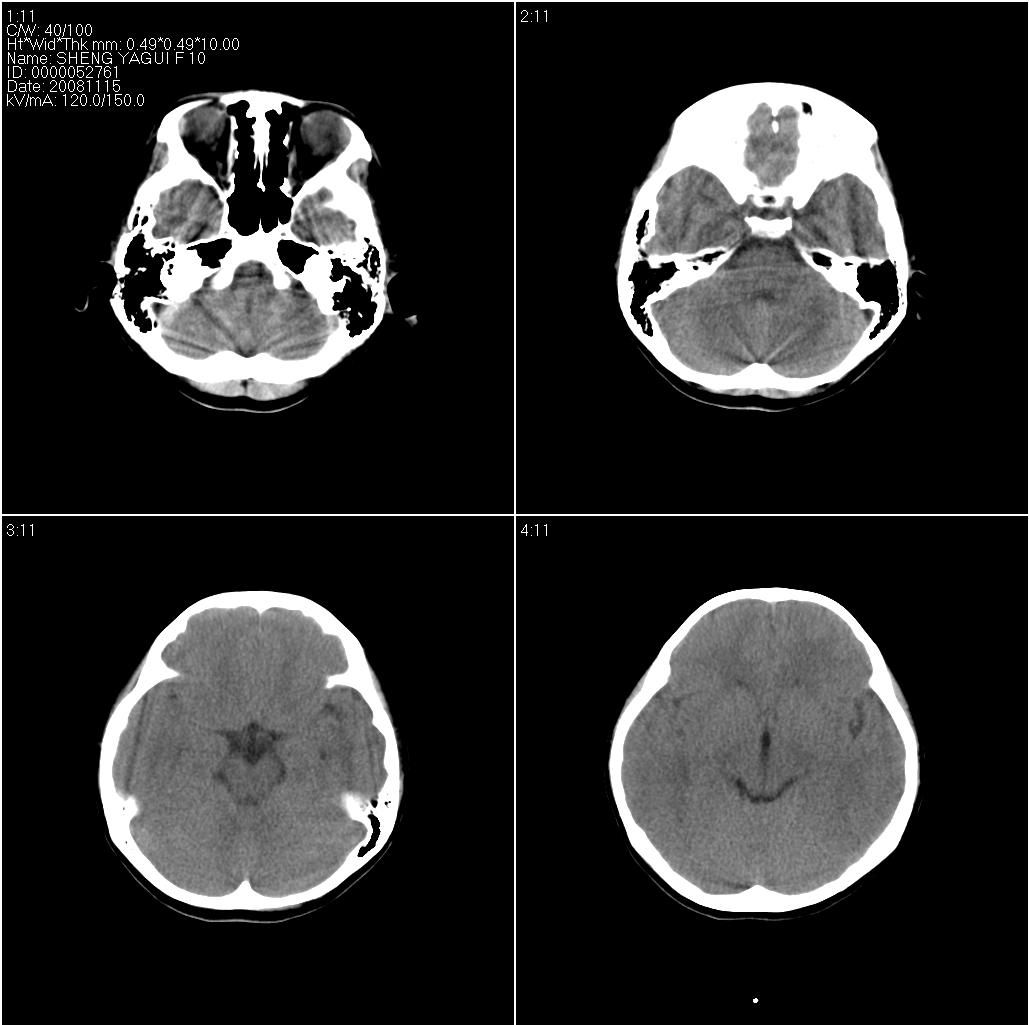

标题: PED1643:女,10岁。抽风两次。 [打印本页]

标题: PED1643:女,10岁。抽风两次。

右侧大脑皮质裂隙,未与脑室相通,应该是脑裂畸形。

主要与脑穿通畸形相鉴别。两者相同点:都是跨越大脑半球的裂隙。不同点:脑裂畸形有皮层灰质沿裂隙内折到脑室壁。穿通畸形:裂隙两缘无皮层内折。脑裂畸形一定合并灰质异位。但灰质异位不一定合并脑裂畸形。

右侧脑裂畸形,灰质异位

右侧脑裂畸形,灰质异位 脑穿通畸形囊肿常有负占位 。

病灶形态及与脑表面的关系,临近脑皮质形态及临近脑沟形态较支持脑裂畸形伴临近脑皮质发育不良,但辐射冠及半卵圆中心层面示病灶与白质间无明显灰质内称,这个不太符合脑裂畸形,因此脑裂畸形首先考虑不除外脑穿通畸形